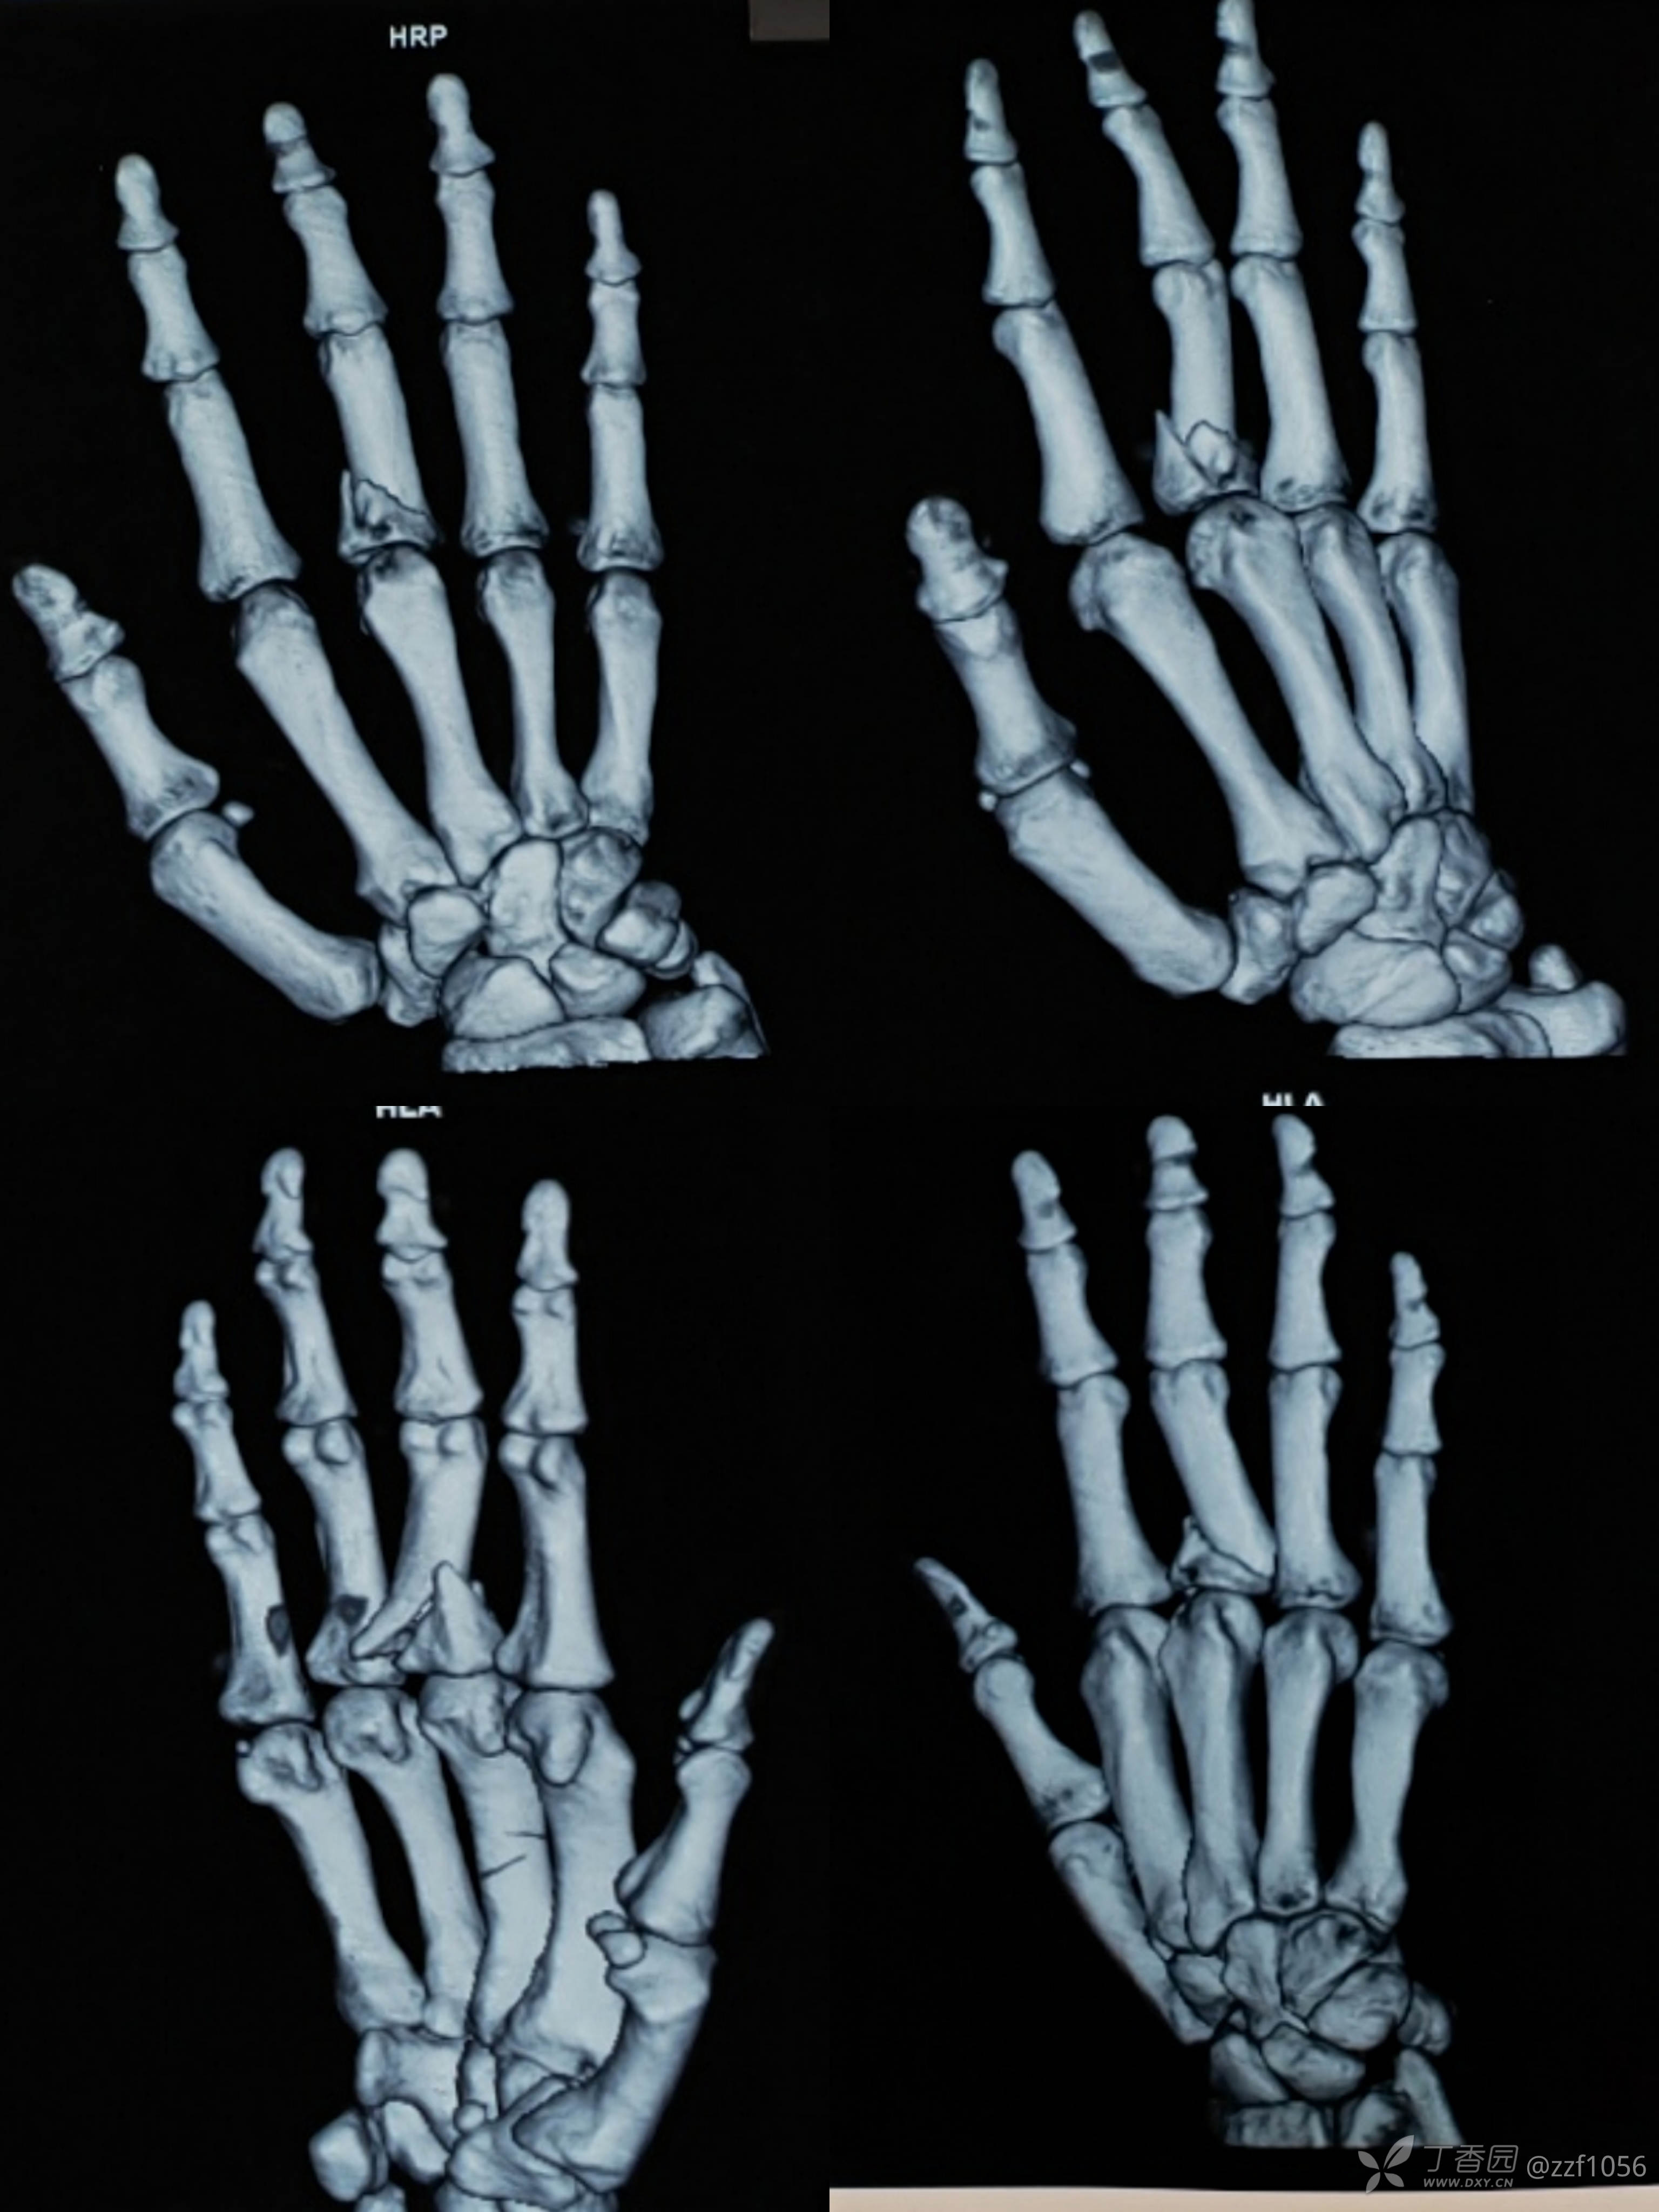

术前

指骨骨折6周愈合情况,愈合相当牢固